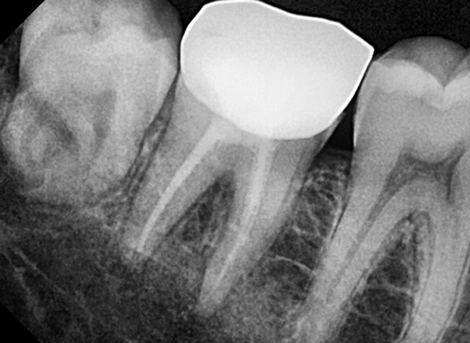

Restoration

With good oral hygiene, it can last a lifetime.